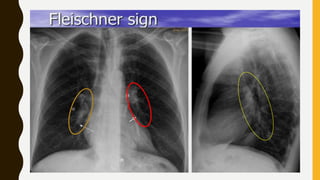

IMAGING

• Chest x-ray is usually normal

Findings, such as

• Focal oligaemia (westermark sign),

• A peripheral wedge-shaped opacity, usually in the

lower half of the lung field (hampton’s hump), or

• An enlarged right descending pulmonary artery

(Pallas’s sign) are rare